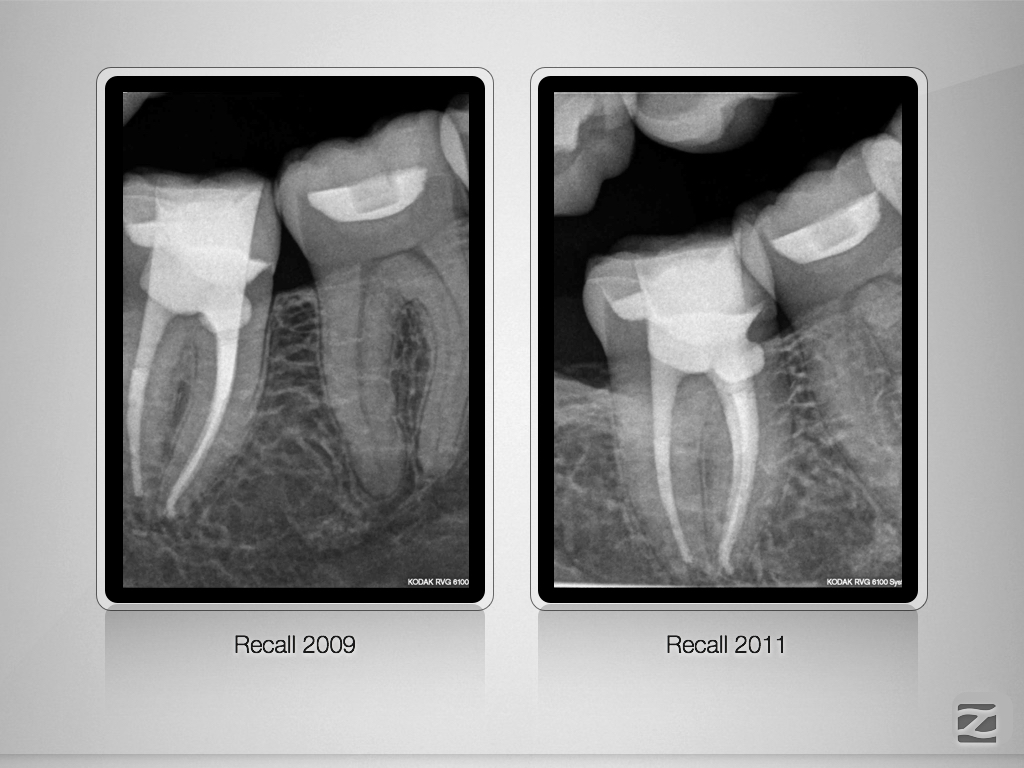

Interne Resorption 10-Jahres-Recall